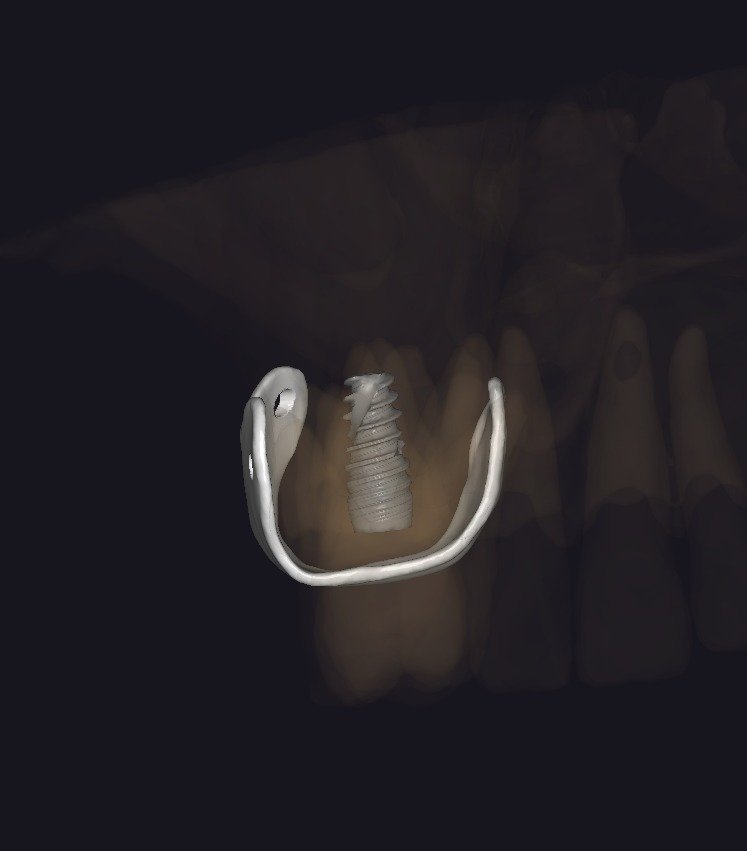

• BlueSkyPlan: diagnóstico, segmentación y análisis del defecto.

• Exoplan / Exocad: diseño digital aplicado a la regeneración.

• Concepto de barrera personalizada.

• Principios de diseño biomecánico.

• Espesor, extensión y bordes de la barrera.

• Diseño pasivo y adaptación milimétrica.

• Planificación de tornillos de fijación:

• Número

• Posición

• Angulación